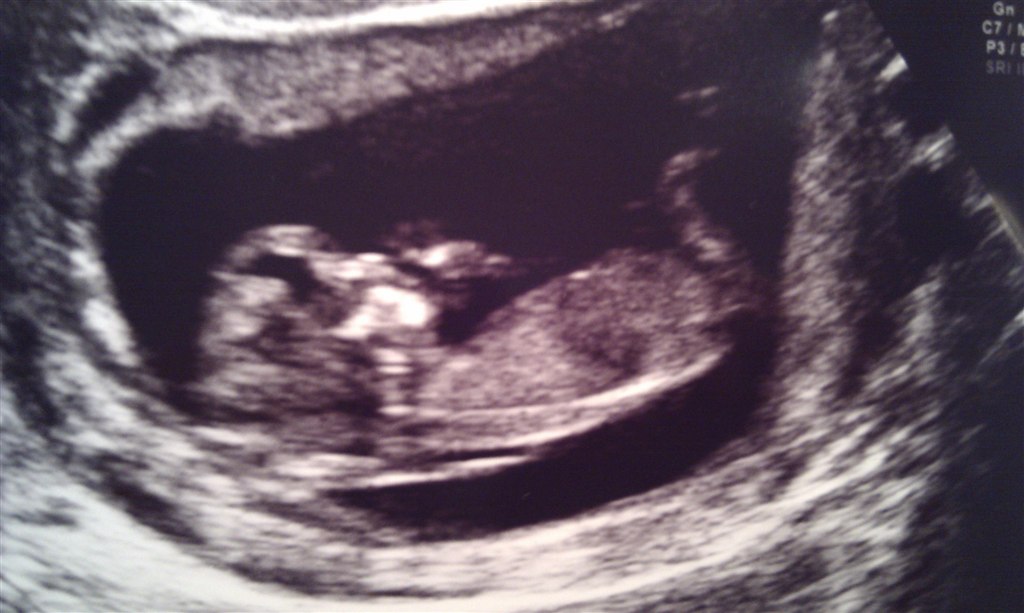

Så har vi været til NF. Sikken oplevelse

Den lille bandit har det efter sigende godt, og risikovurderingen lød på 1:18493.. Så vi tager det ganske roligt

Den lille drillede jordemoderen, og vendte ryggen til, hver gang hun ville scanne.

Og så ville den meget gerne sutte på tommel. Det er det hun har prøvet at fange et billede af her

Termin flyttet 1 dag, til 22.06.11.

Bjørnen er bare et stort smil, og har lagt billede på FB og ja.. Er bare meget glad, og nok også lidt mere forstående. For nu har han set en helt rigtig baby, inde i min mave. Fantastisk syn.. Vi var der i 20 minutter, men jeg ville stadig kunne ligge der nu og kigge. Et syn man aldrig bliver træt af!